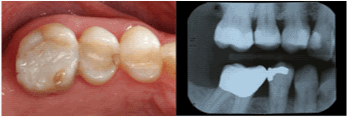

| Mandibular Left First

Molar |

8 |

73.8% |

|

6 |

82.9% |

| Maxillary Right First

4 |

89.2% |